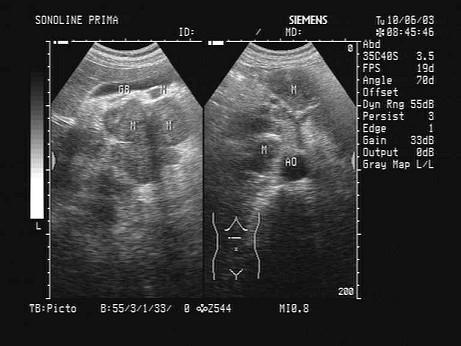

某患者肝门及腹腔可见多个肿块回声。根据声像图表现,最可能的诊断是?(?)A.肝癌B.胰腺癌C.肠系膜肿瘤D.肿大淋巴结E.以上都不是

问题 某患者肝门及腹腔可见多个肿块回声。根据声像图表现,最可能的诊断是?(?)

选项 A.肝癌 B.胰腺癌 C.肠系膜肿瘤 D.肿大淋巴结 E.以上都不是

答案 D